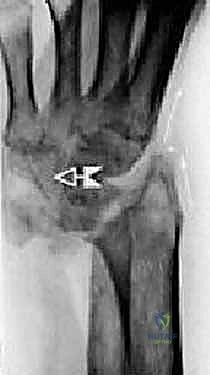

1. التخطيط الجراحي المسبق

قبل العملية، يتم إجراء صور أشعة سينية (X-rays) وأشعة مقطعية (CT scan) ثلاثية الأبعاد. تساعد هذه الصور الدكتور هطيف في تحديد حجم التلف بدقة، واختيار الحجم والنوع المناسب للمفصل الصناعي (والذي يتكون عادة من أجزاء معدنية من التيتانيوم ومكونات بلاستيكية عالية الكثافة من البولي إيثيلين).